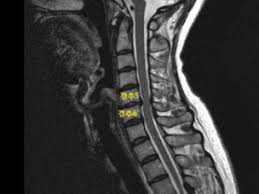

목디스크는 경추와 흉추 부위에서 발생할 수 있으며, 이러한 디스크의 변화는 주로 디스크의 손상된 부분이 주변 신경을 압박하거나 자극함으로써 다양한 증상을 유발합니다.

목디스크는 하중이 한 부위에 집중되어 경추 사이에 있는 추간판이 파열되고 내부의 수핵이 변위될 수 있는 상태를 가리킵니다.

이러한 상태는 공식적으로는 경추 추간판 탈출증으로 알려져 있으며, 목의 추간판이 손상되어 통증과 불편을 초래할 수 있습니다. 목디스크는 일상 활동에서의 부적절한 자세나 무리한 운동, 또는 직업적 요인으로 발생할 수 있습니다.